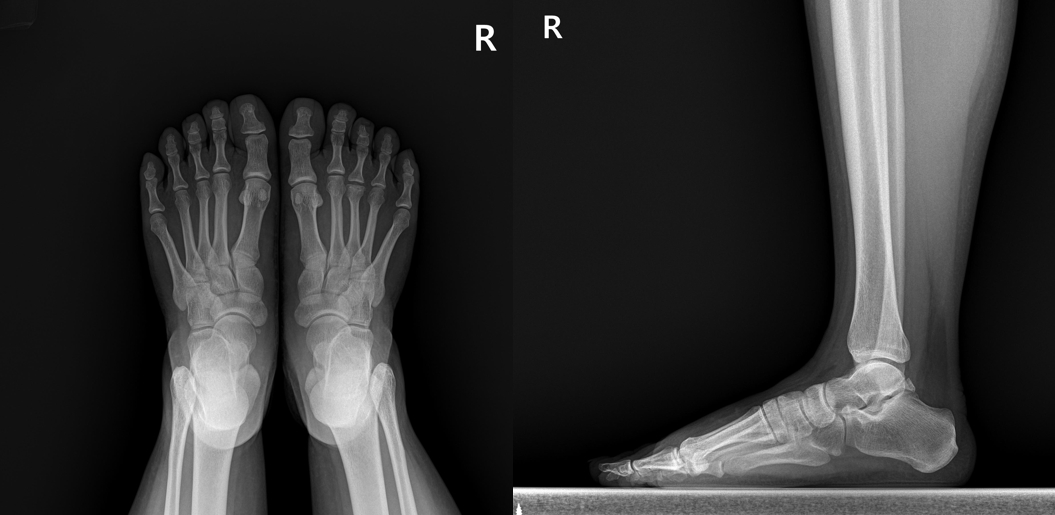

X-ray를 촬영했는데...

검사상에서는 특별한건 없습니다. 이유없이 발이 아프다는 분들의 경우 평발이나 요족인 경우가 종종 있는데 이 여성분의 발은 평발도 요족도 아닌 상태로 보였습니다. 그래서 초음파 검사를 했습니다. 그 결과는...